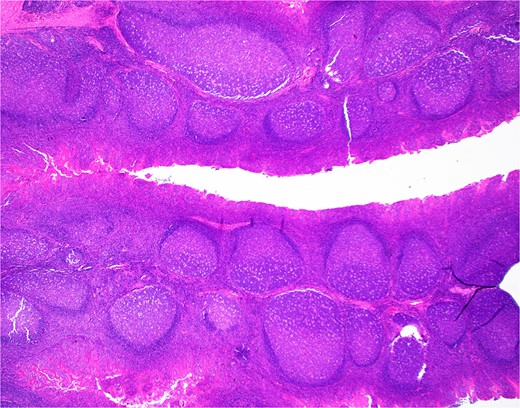

The patient’s bilateral tonsillectomy (Fig. 1) showed follicular and MZH with follicles demonstrating intact architecture, definitive polarity, and frequent tingible body macrophages. Flow cytometric analysis detected a decreased Kappa:Lambda ratio among the B cells present in both the left and right tonsil specimens, and they showed similar patterns. The Kappa:Lambda ratio ranged from 0.34 to 0.59 among differentially gated B cell populations. The Kappa:Lambda ratio remained low regardless of gating on CD10(+), CD38(+) germinal center B cells (Fig. 2h), versus CD38(−) B cells (Fig. 2f). Approximately 26.74% of all CD20(+) B cells were at least dimly CD27(+) (Fig. 2i), with the majority of B cells having a naïve immunophenotype, expressing mostly IgM (Fig. 2k), IgD (Fig. 2j), and lacking CD27. When gating on the naïve CD27(−), CD38(−) B cells, the Kappa:Lambda ratio remained low, 0.45 (Fig. 2j).

H&E section from Case 1 tonsillectomy. Representative H&E section (20×) of Case 1 tonsillectomy showing intact architecture, follicular and MZH with follicles having definitive polarity and abundant tingible body macrophages.